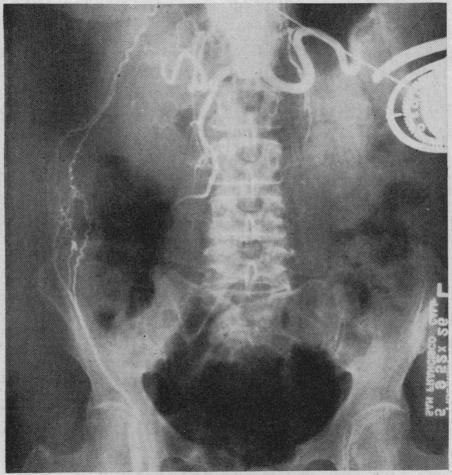

With the use of anticoagulants to prevent recurrence of thrombosis it is now possible to open a major artery which has been occluded by a thrombus, remove the thickened lining with the clot and restore the continuity of the vessel. Free vein grafts have been used successfully to replace arterial segments in the extremities. Vein inlay grafts are preferred in dealing with aneurysms of the abdominal aorta. The aneurysmal wall can be used to support the venous segments. It has been possible to by-pass aneurysms of the abdominal aorta by anastomosing the splenic artery to the left iliac artery. The use of the left superficial femoral artery as a by-pass to supply blood to the right leg is described.

使用抗凝剂预防血栓形成复发后,现在有可能开通一条被血栓阻塞的主要动脉,清除带有血栓的增厚内膜并恢复血管的连续性。游离静脉移植物已成功用于替代四肢的动脉段。在处理腹主动脉瘤时,静脉镶嵌移植物更受青睐。动脉瘤壁可用于支撑静脉段。通过将脾动脉与左髂动脉吻合,有可能绕过腹主动脉瘤。文中描述了使用左股浅动脉作为旁路为右腿供血的情况。